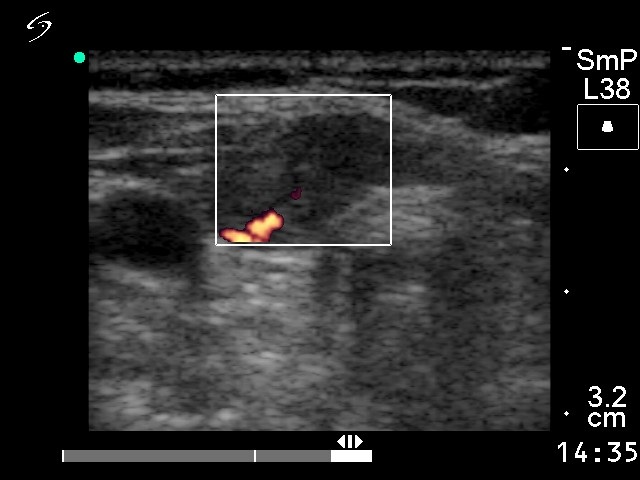

Ultrasonography revealed a hypoechogenic mass in the right lobe and in the isthmus with small cystic areas. The nodule was avascular on Doppler mode.